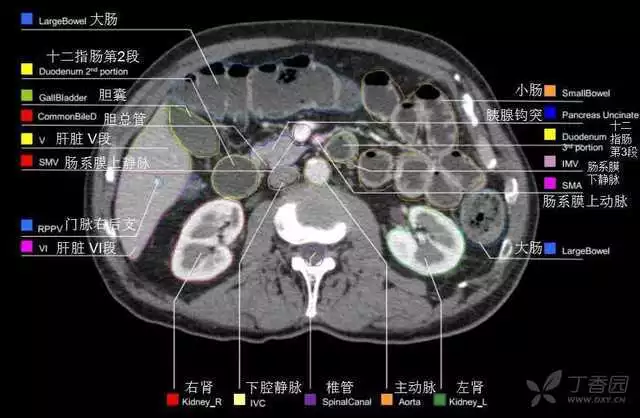

其实你离掌握上腹部 CT 影像只有一套高清实用图谱的距离,下面把我最喜欢的这本图谱分享给大家,为了方便阅读,我加了中文标识。后面附赠几张血管相对位置解剖关系图片,帮助大家理解(文中多图,建议在 wifi 环境下查看)。